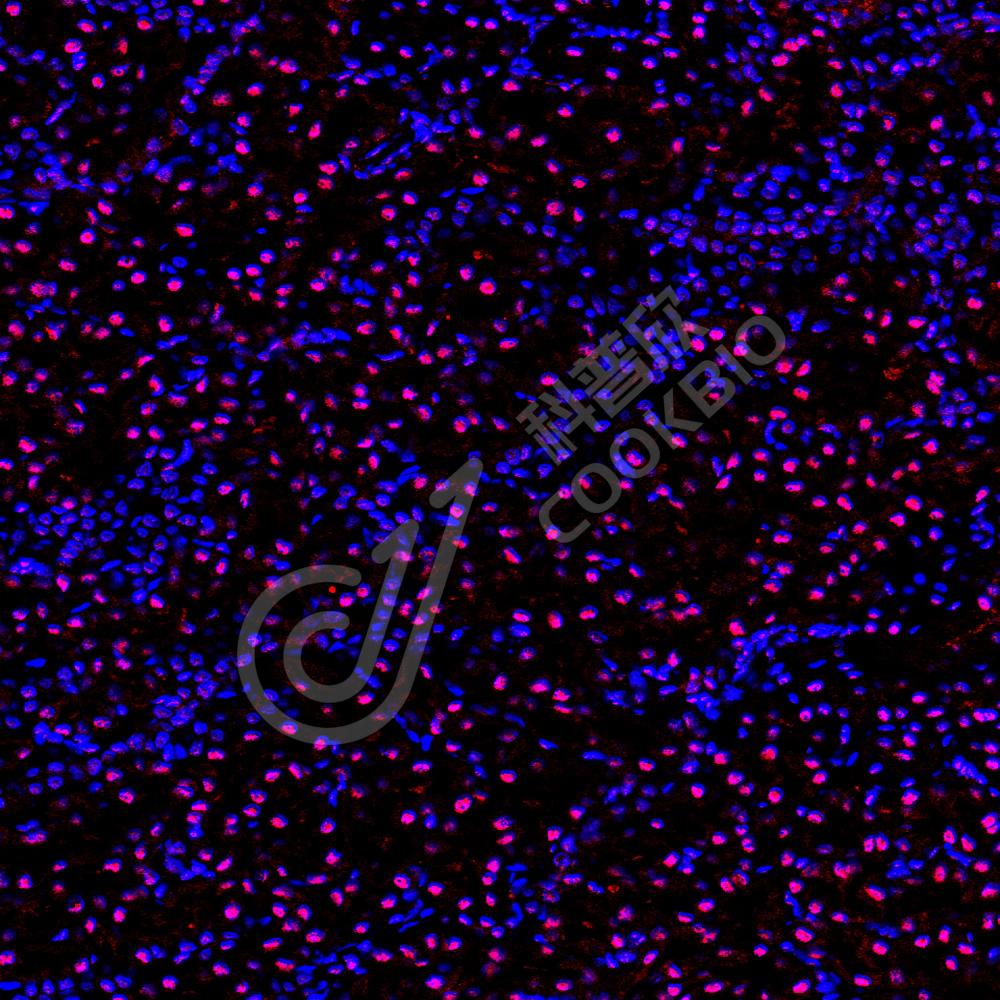

IF检测Serum Response Factor SRF蛋白(货号 K1333144)(红色).

样品: 小鼠心, 4%多聚甲醛 (货号KSG1101) 固定12-24小时.

抗原修复: Tris-EDTA抗原修复液(pH 9.0) (KSG1203), 98℃, 20分钟.

封闭: 3% BSA(货号KSGC305010)的PBS溶液, 室温孵育30分钟.

—抗: 1: 1800稀释, 4℃ 孵育过夜.

二抗: Cy3标记山羊抗兔IgG (H+L) (货号KB63909), 1: 300稀释, 室温孵育1小时.